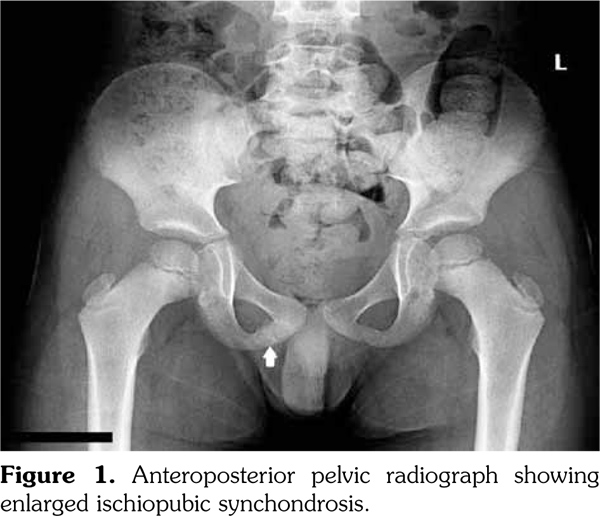

A seven-year-old male patient with left foot dominance presented to a medical center with severe acute right groin pain. There was no history of trauma. He could not bear weight on his right limb, pain was localized in the groin, radiating to the knee. He was unable to raise his leg and hip adductor muscles were very tender to touch. Range of motion of right hip was very painful and restricted. Laboratory tests revealed slightly increased leukocytes with normal CRP and ESR. Anteroposterior radiographs of the pelvis showed enlarged right IPS characterized by focal areas of osteolysis (Figure 1). Hip magnetic resonance imaging (MRI) showed hypointense sclerotic corticomedullary discontinuity at anterior of right ramus pubis (Figure 2a) together with edema of perilesional soft tissue and muscles (Figure 2b). These findings were misinterpreted as a subacute fracture. The patient was recommended bed rest and analgesics and he recovered after three weeks. A written informed consent was obtained from the patient.